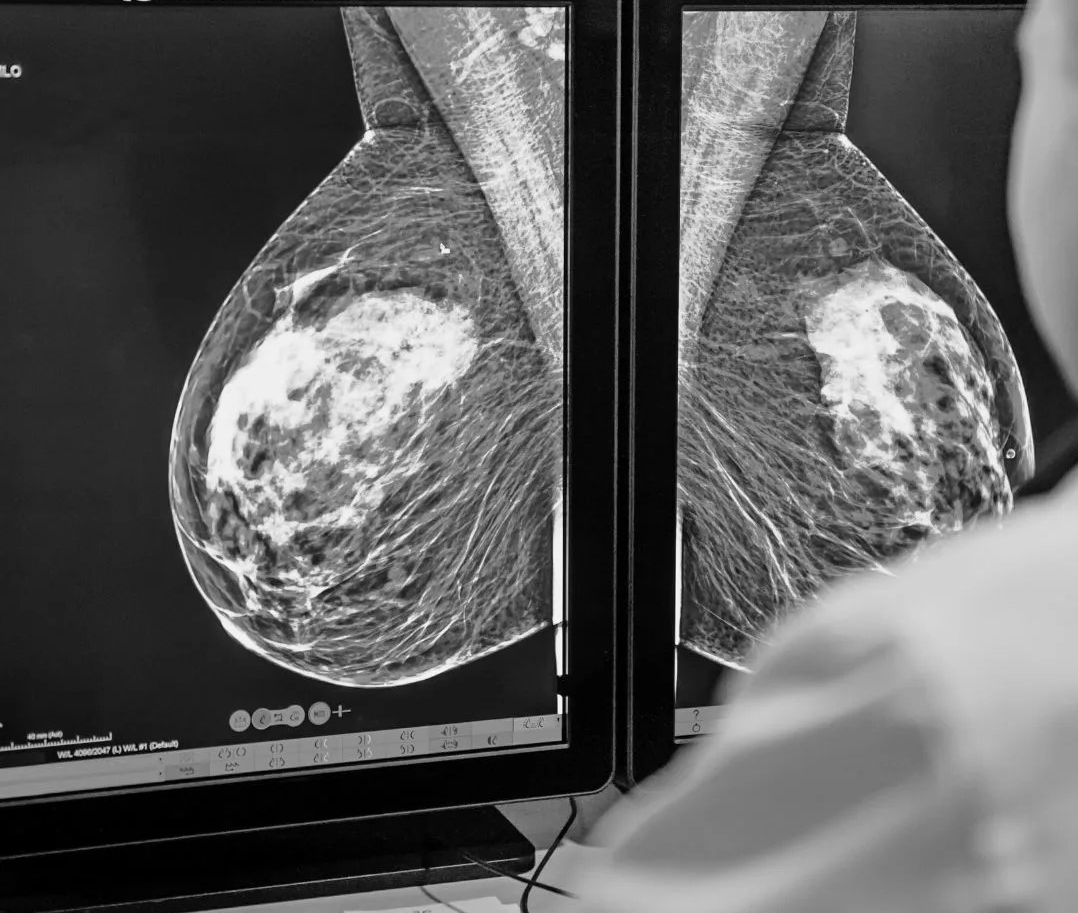

Sự khác biệt giữa chụp nhũ ảnh sàng lọc và chụp nhũ ảnh chẩn đoán ung thư vú- Ảnh 1.

Chụp nhũ ảnh sàng lọc được thực hiện ngay cả trước khi bất kỳ triệu chứng nào của ung thư vú xuất hiện.

Chụp nhũ ảnh hay chụp X-quang tuyến vú (Mammography) là kỹ thuật sử dụng chùm tia X cường độ thấp chiếu vào các mô tuyến vú để thu lại các hình ảnh tại tuyến vú. Phương pháp này giúp phát hiện các bất thường, khối u ở giai đoạn sớm ngay cả khi bệnh nhân chưa sờ và cảm nhận thấy.